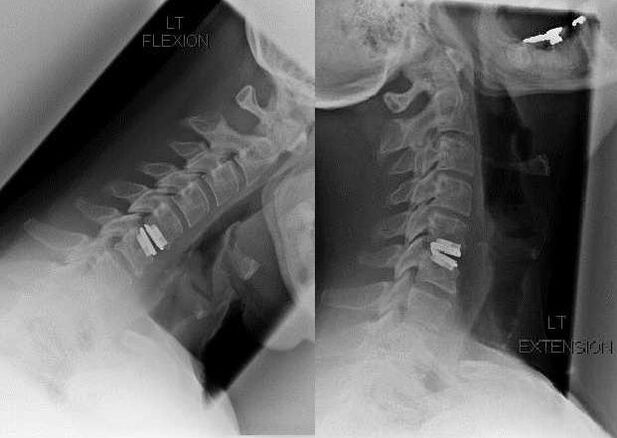

Ihe ngosi maka itinye aka na ịwa ahụ gụnyere ịgwọ ọrịa osteochondrosis, dịka ihe atụ, disfulath akwara, na radicular ọrịa. Iji degharịa eriri azụ, arịa ọbara, na mgbọrọgwụ spadinal, a na-arụ ọrụ ndị a:

N'oge awa ahụ, iberibe ọkpụkpụ na ligam nwere ike iwepụta, yana diski interfetral nwere ike ịbụ kpam kpam ma ọ bụ wepụrụ. Maka obere ụlọ ọgwụ, na -adị veporization nke diski diski a na-arụ.

Mgbe ịchasịrị nke vertebral owuwe, mma nke akụkụ ngagharị na-abụkarị site na ngwakọta spain ma ọ bụ nrụnye nke ọkpụkpụ na dermal.